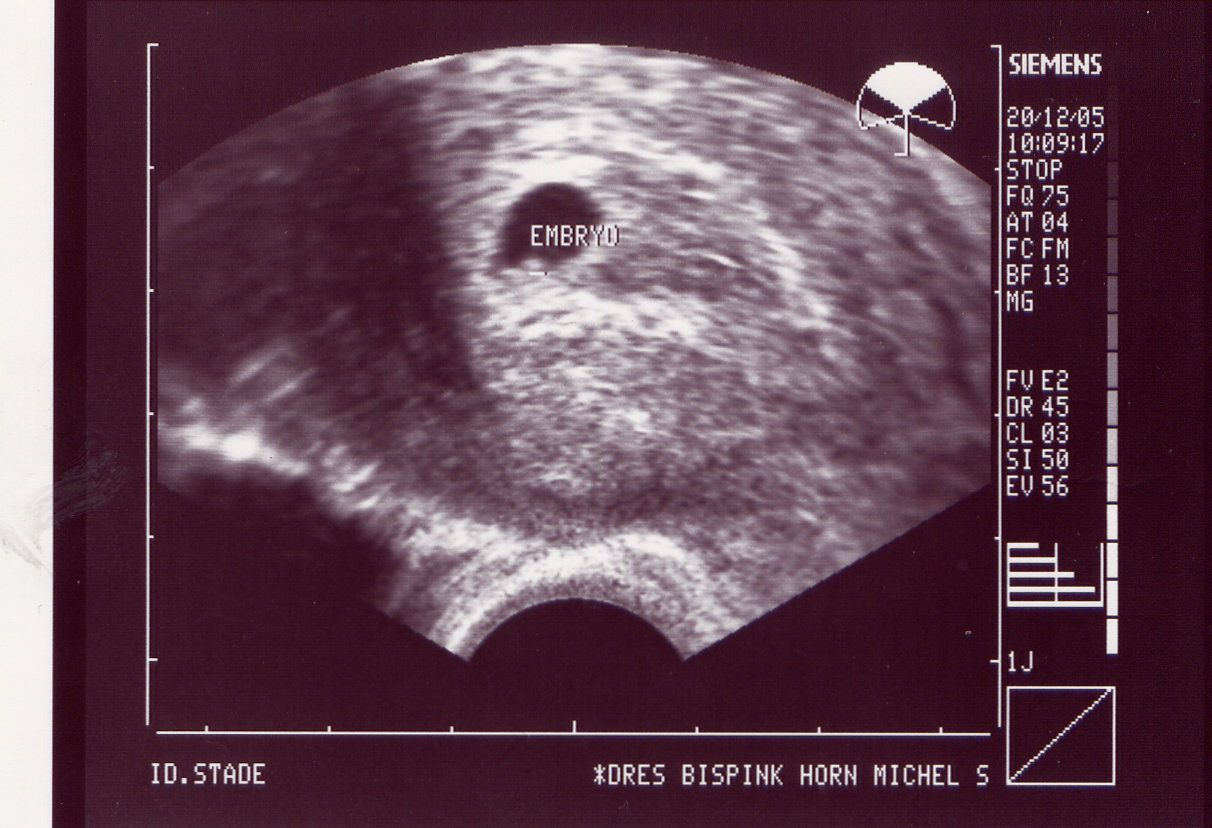

ich habe heute 5 US-Bilder eingescannt und 2 davon waren gut zu erkennen, der Rest

20.12.05 Herzchen schlägt 6+0 HCG 3853

Das Organscreening wird wiederum aufgrund meines Alters gemacht und weil ich durch künstliche Befruchtung schwanger geworden bin. Mein Arzt geht da lieber auf Nr. sicher. Ihr wißt doch, daß einem nur noch 3 US-Bilder zur Verfügung stehen und ich hab doch schon 5, zwei davon wurden mir geschenkt

Aber leider sind die US-Bilder von meinem Haus-Gyn so dunkel, daß diese ganz schlecht zu scannen sind, wie ihr vielleicht schon gesehen habt. Habt ihr sonst einen Tip?